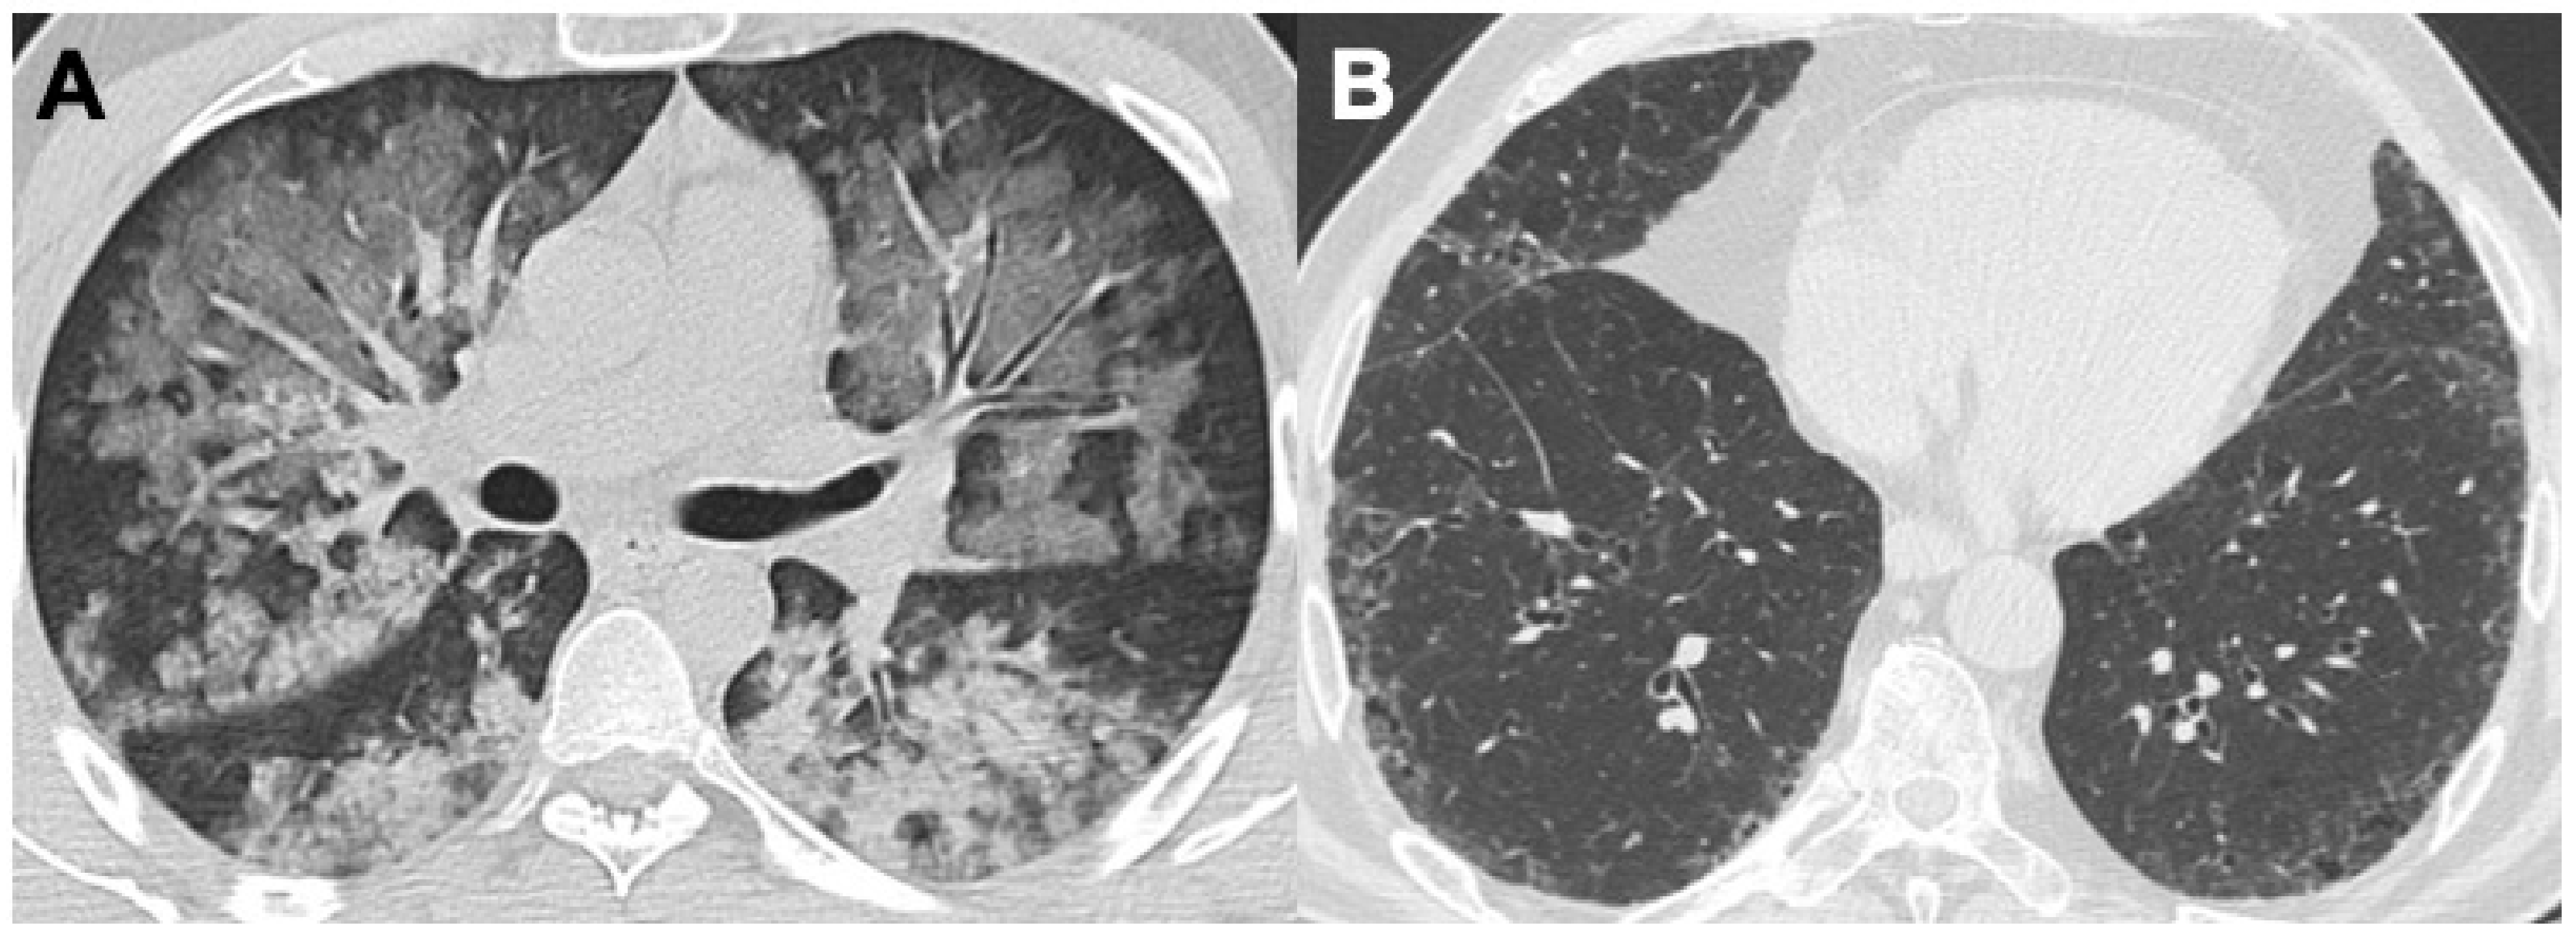

2.4. Microscopic Polyangiitis (MPA)

| MPA | Bronchiectasis (40%) | GGO (23–94%); reticular changes (UIP, NSIP, and DIP patterns); consolidations; diffuse alveolar hemorrhage (25–60%) | Pleural effusion; pleuritis | |